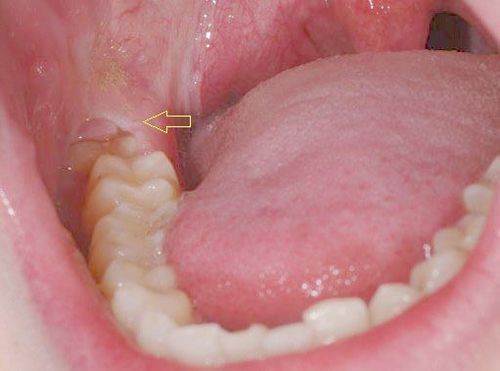

Lưu ý với răng khôn mọc ngầm

Bất cứ răng nào cũng có thể mọc ngầm, tuy nhiên phổ biến nhất đó là răng khôn mọc ngầm. Dấu hiệu răng khôn mọc ngầm thường bị nhầm lẫn với mọc răng khôn thông thường. Vậy răng khôn mọc ngầm là như thế nào, răng khôn mọc ngầm có nên nhổ không?

Quá trình mọc răng khôn diễn ra trong bao lâu?

Răng khôn luôn là nỗi ám ảnh đối với nhiều người, quá trình mọc răng khôn luôn đi kèm với cảm giác khó chịu và đau đớn. Vậy bạn đã hiểu rõ quá trình mọc răng khôn trong bao lâu hay chưa? Cùng tìm hiểu qua bài viết sau.